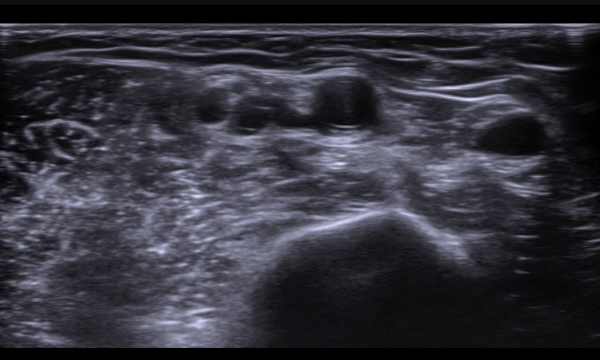

ÃÊÀ½ÆÄ  °Ë»ç  : À­ÆÈ ±ÙÀ§ºÎ Á¤Áß ½Å°æ Ⱦ´Ü¸é°Ë»ç¿¡¼­ Á¤Áß ½Å°æÀÇ ºÎÁ¾°ú ÀϺΠ½Å°æ¼¶À¯ÀÇ Àú¿¡ÄÚ ºÎÁ¾ÀÌ °üÂûµÈ´Ù

(»çÁø 1, 2). ŽÃËÀÚ¸¦ Á¶±Ù ´õ ±ÙÀ§ºÎ·Î À̵¿ÇÏ´Ï Á¤Á߽ŰæÀÇ Àú¿¡ÄÚ ºÎÁ¾ÀÌ °üÂûµÈ´Ù(»çÁø 3, 4).